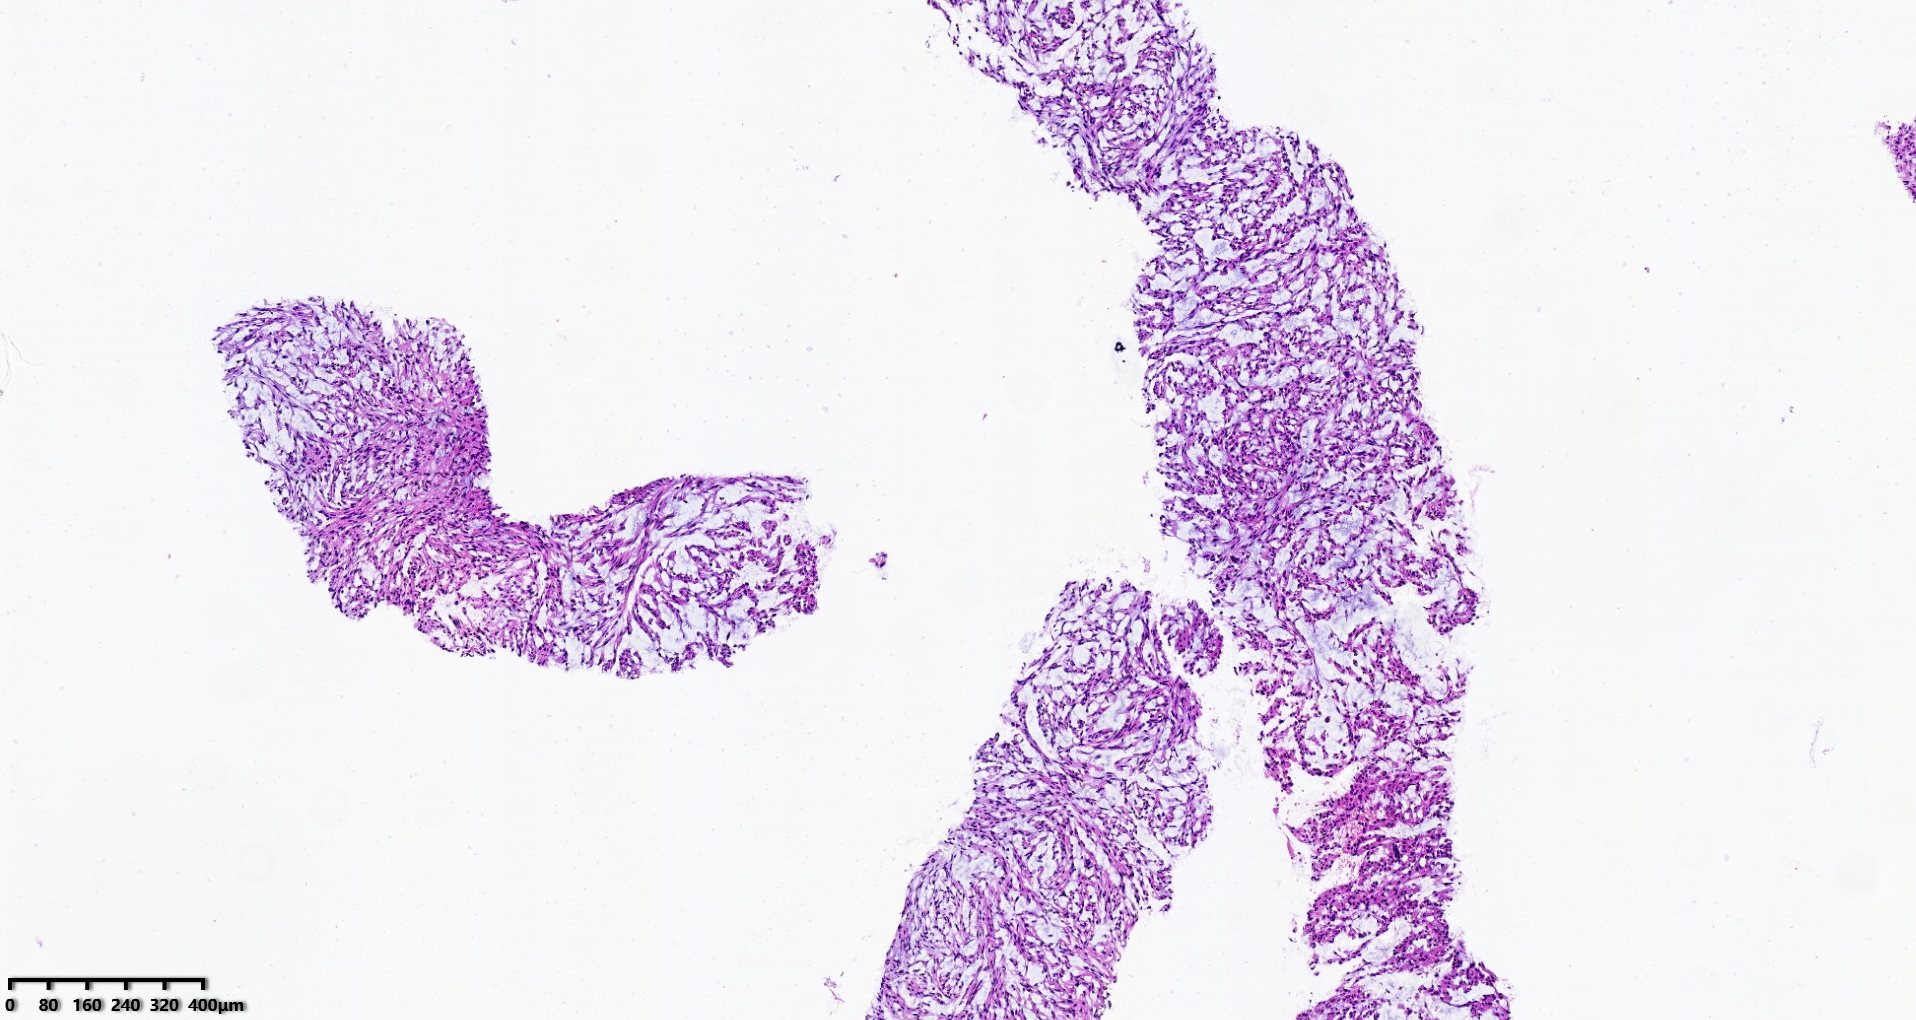

腹盆腔穿刺

腹盆腔肿物10.5×21.5cm大小

穿刺组织1.0×1.0cm

S100、CD34、MDM2、STAT6、CD117、CK均阴性

图1

考虑:深部软组织平滑肌肉瘤